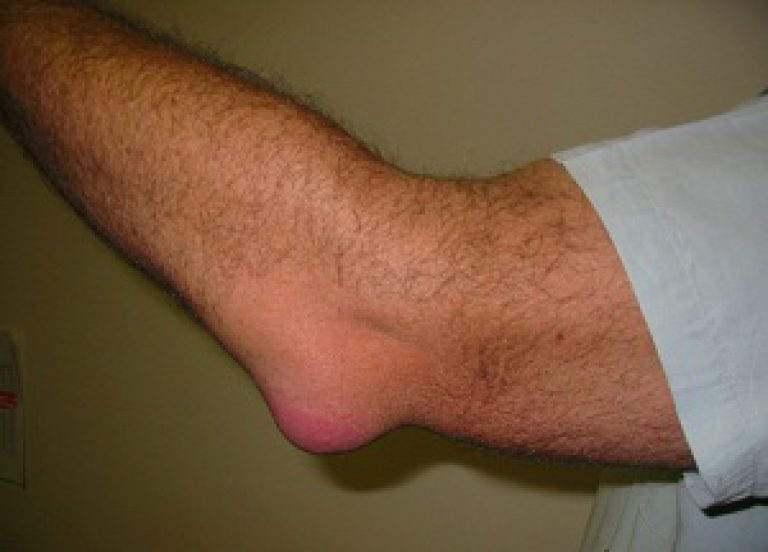

На начальном этапе развития артрит проявляется общим недомоганием, которое человек принимает за переутомление. Его также беспокоят слабые дискомфортные ощущения в локте, немного ограничивающие подвижность. Но их выраженность быстро повышается. Теперь при сгибании и разгибании сустава возникают сильные, острые или тупые, ноющие боли. Вскоре к ним присоединяются и другие симптомы артрита:

- увеличиваются размеры пораженного артритом локтя по сравнению со здоровым суставом;

- кожа краснеет, становится горячей на ощупь;

- при сгибании или разгибании локтя слышатся щелчки, хруст, потрескивание;

- скованность движений становится постоянной.